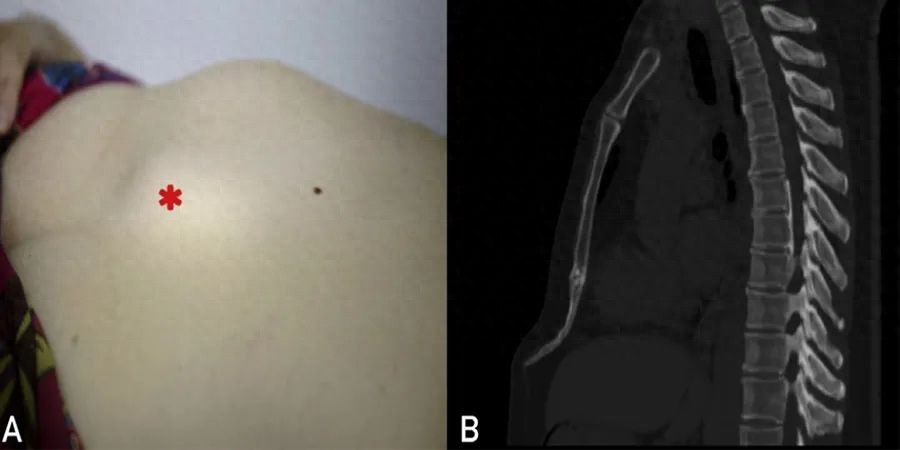

上腹部中部可见肿块,仰卧位时尤为明显(图 A)。

CT显示一个细长弯曲的剑突(图 B)。

测量的剑突长度、宽度和厚度分别为63.2mm(参考范围,40-50mm)、21.1mm(参考范围,15-20mm)和4.9mm(参考范围,3-5mm)。胸骨体至剑突的角度为138°(参考范围160°-180°)。